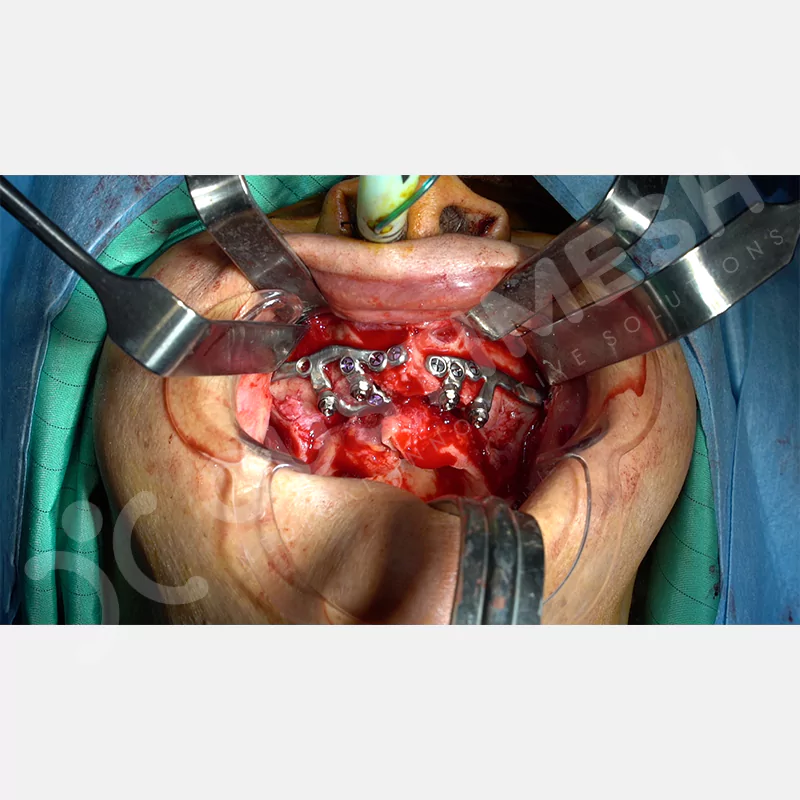

Modern diş hekimliğinde, çene gelişimini tamamlamamış veya ciddi kemik kaybı yaşayan hastalar için kişiye özel titanyum implantlar ile çözüm bulunmaktadır. CAD/CAM teknolojisi ve lazer sinterleme yöntemiyle üretilen bu implantlar, hastanın bireysel anatomik yapısına tam uyum sağlayarak geleneksel implantların uygulanamadığı vakalarda mükemmel bir alternatif oluşturmaktadır. Özellikle ileri derecede kemik kaybı olan hastalar için geliştirilen subperiosteal implantlar, periostun altına yerleştirilerek minimal invaziv bir yaklaşım sunarken, bilgisayarlı tomografi verileri ve sonlu eleman analizleriyle optimize edilmiş tasarımları sayesinde hem estetik hem de fonksiyonel sonuçlar garanti etmektedir. Bu yenilikçi teknoloji, tek seansta implant ve protez uygulamasına imkan vererek hastaların aynı gün doğal gülüşlerine kavuşmalarını sağlarken, kemik greftleme gibi ek işlem ihtiyacını ortadan kaldırarak cerrahi süreci büyük ölçüde kolaylaştırmaktadır. Kişiye özel tasarımı ve üstün biyouyumluluğu sayesinde, daha önce tedavisi mümkün görülmeyen kompleks vakalarda bile başarılı sonuçlar sunan bu implantlar, modern diş hekimliğinde yeni bir çağ açarak hastaların yaşam kalitesini artırmayı hedeflemektedir.

VAKA 1

VAKA 2

VAKA 3

VAKA 4